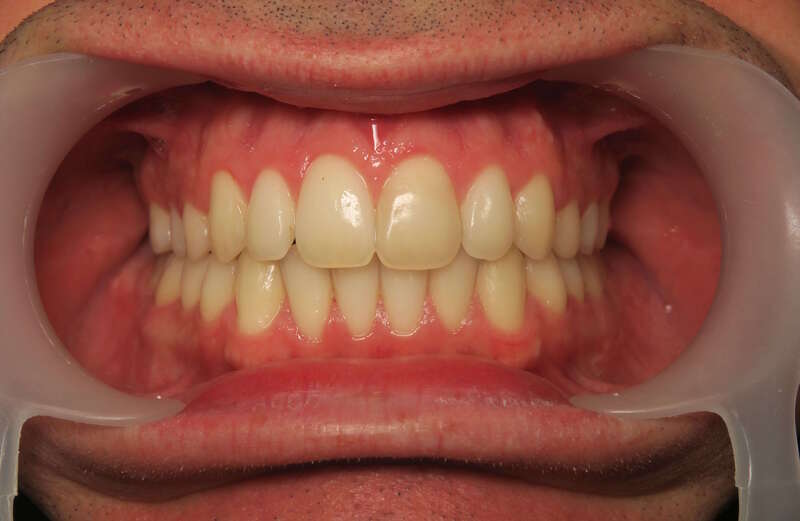

Cas n°1 traité par aligneurs (interception) - enfant

Ce cas d’interception chez un enfant de 8 ans démontre l'efficacité des aligneurs pour corriger des troubles fonctionnels précoces. Le diagnostic présentait des inversions d'articulé provoquant une déviation de la mandibule vers la gauche et un décalage des milieux.

Grâce à une coopération exemplaire et un traitement totalement indolore, l'expansion de l'arcade a permis de recentrer la mâchoire. Cette intervention a littéralement remis la croissance sur les rails, neutralisant le risque d'asymétrie faciale squelettique.

• Correction fonctionnelle : Recentrage immédiat de la mandibule et des milieux inter-incisifs.

• Prévention : Création d'un environnement favorable pour les dents définitives à venir.

• Bien-être : Approche douce respectant le confort de l'enfant.

C'est une étape fondamentale qui simplifie l'avenir orthodontique du patient tout en garantissant un développement facial harmonieux.

Avant

Après